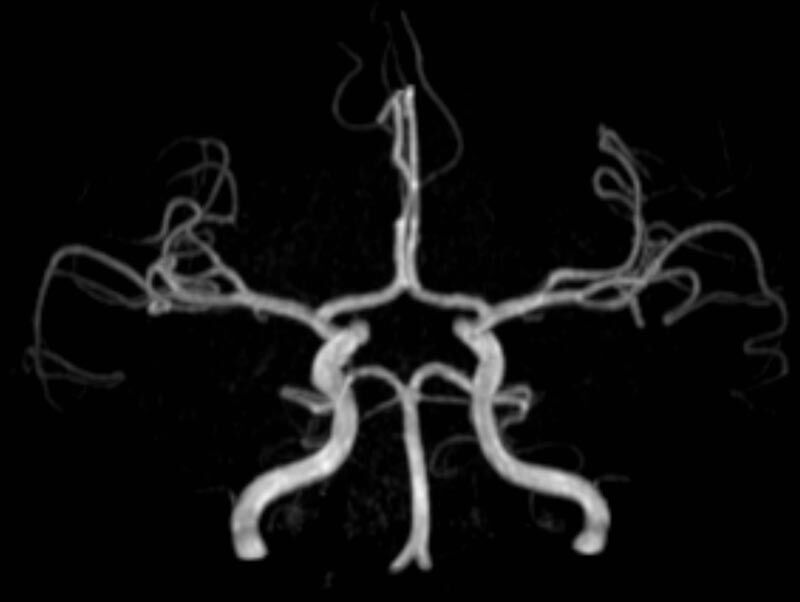

- MR-Angiografie ohne Kontrastmittel

- Time of Flight (TOF)-Angiographie

Je nach Fragestellung und Körperregion Gefäßdarstellung ohne Kontrastmittel bei Kontrastmittelunverträglichkeit oder terminaler Niereninsuffizienz möglich.

- MR-Angiographie mit Kontrastmittel

- Erfassung arterieller und venöser Gefäße/Bypässe aller Körperregionen mit 3D-Rekonstruktion